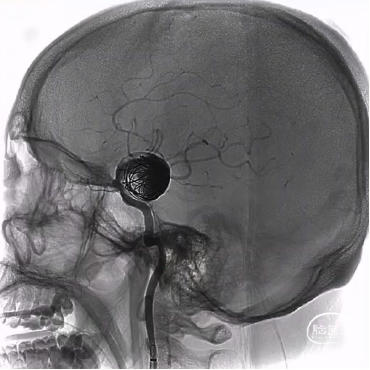

颈内动脉狭窄状况及闭塞试验

1. 术后一周复查DSA显示动脉瘤无血流,桥血管通畅。